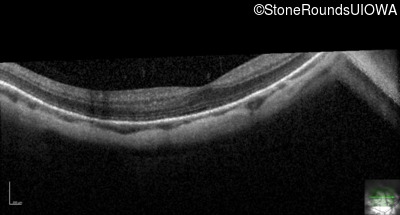

Age at visit: 28 years

OD OS